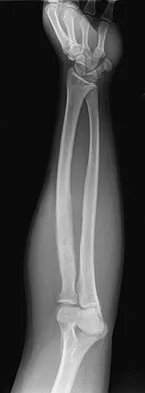

A 30-year-old man has pain in the left arm after a motor vehicle accident. His neurovascular examination is intact, and radiographs are shown in Figures 25a and 25b. What is the best course of management?

Explanation

The floating elbow is best managed with early open reduction and internal fixation of the humeral and forearm fractures, followed by early range of motion. These fractures predispose the elbow to stiffness, and early range of motion is recommended. Solomon HB, Zadnik M, Eglseder WA: A review of outcomes in 18 patients with floating elbow. J Orthop Trauma 2003;17:563-570.